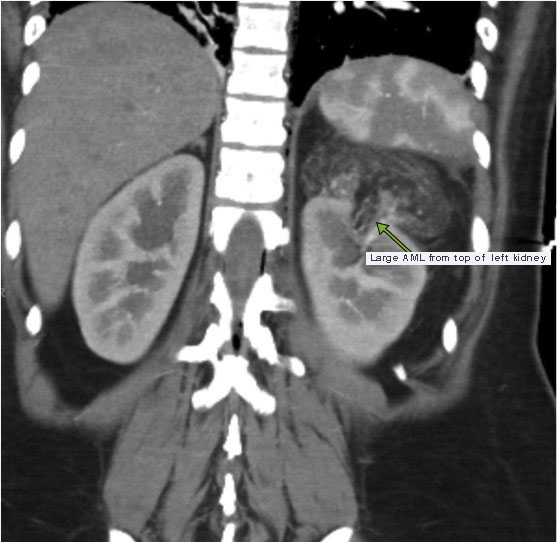

When these tumors are greater than 4 cm there is a high risk of spontaneous life-threatening hemorrhage. This CT scan shows a large (8 cm) angiomyolipoma at the top of this patient’s left kidney.